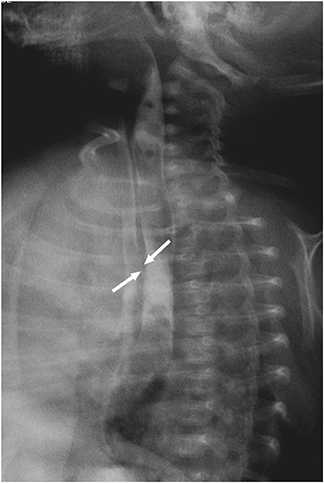

Routine esophagogram taken on postoperative day 10 still showed an evidence of fistula (

Fig. 3). Recurrence or presence of another H-type fistula had been suspected. To confirm the diagnosis, rigid bronchoscopy was scheduled under general anesthesia on postoperative day 15. However, the bronchoscopy failed to demonstrate the opening of the fistulous tract even under positive ventilation.

Fig. 3 Another H-type fistula at T2 level.

When feeding was started assuming that the esophagogram showed contrast aspiration, cyanosis and pneumonitis recurred, only less severely than the preoperative days. The baby was treated with antibiotics and kept being fed per oral. He suffered from recurrent pneumonitis.